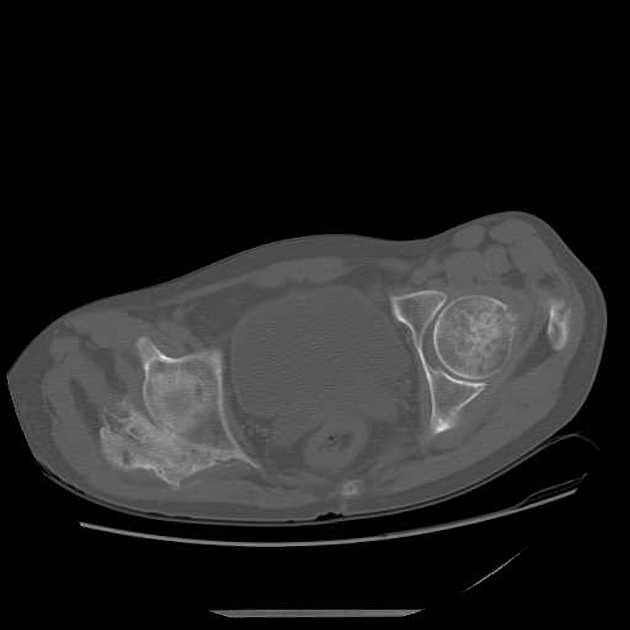

CT may be useful in the visualization of a lesion. Figure 3 demonstrates a lesion posterior to the right acetabulum. It demonstrates a partially corticated periphery and partial cleft separating the lesion from the acetabulum. Figure 4 is an interesting example of an MO lesion in the paraspinal musculature, with ossified periphery and lucent center.